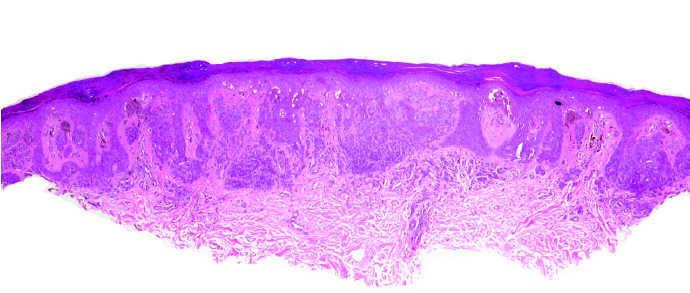

A la exploración se observaron más de 30 máculas pigmentadas de 1 a 4 mm de diámetro en ambas plantas (fig. 1), lo que contrastó con la ausencia de lesiones en el dorso de los pies y el discreto número de nevos melanocíticos en el resto del cuerpo. Macroscópicamente todas las lesiones eran homogéneas en forma y color y el estudio por epiluminiscencia mostró tres patrones diferentes: paralelo al surco, en celosía y fibrilar. El estudio histológico de una de las lesiones mostró una neoplasia simétrica y bien delimitada constituida por nidos uniformes de melanocitos en la unión dermoepidérmica y dermis superficial (fig. 2). Los melanocitos no mostraron signos de atipia ni mitosis.

Fig. 2.--Nidos uniformes de melanocitos en la unión dermoepidérmica y dermis superficial. (Hematoxilina-eosina, ×10.)